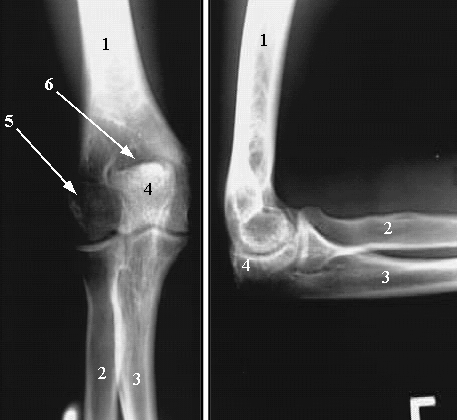

Upper Limbs: X-ray Two Views:

Left View:

1. Humerus

2. Radius

3. Ulna

4. Olecranon Process of the Ulna

5. Leteral Epicondyle

6. Olecranon Fossa.

Right View:

4. Olecranon process.